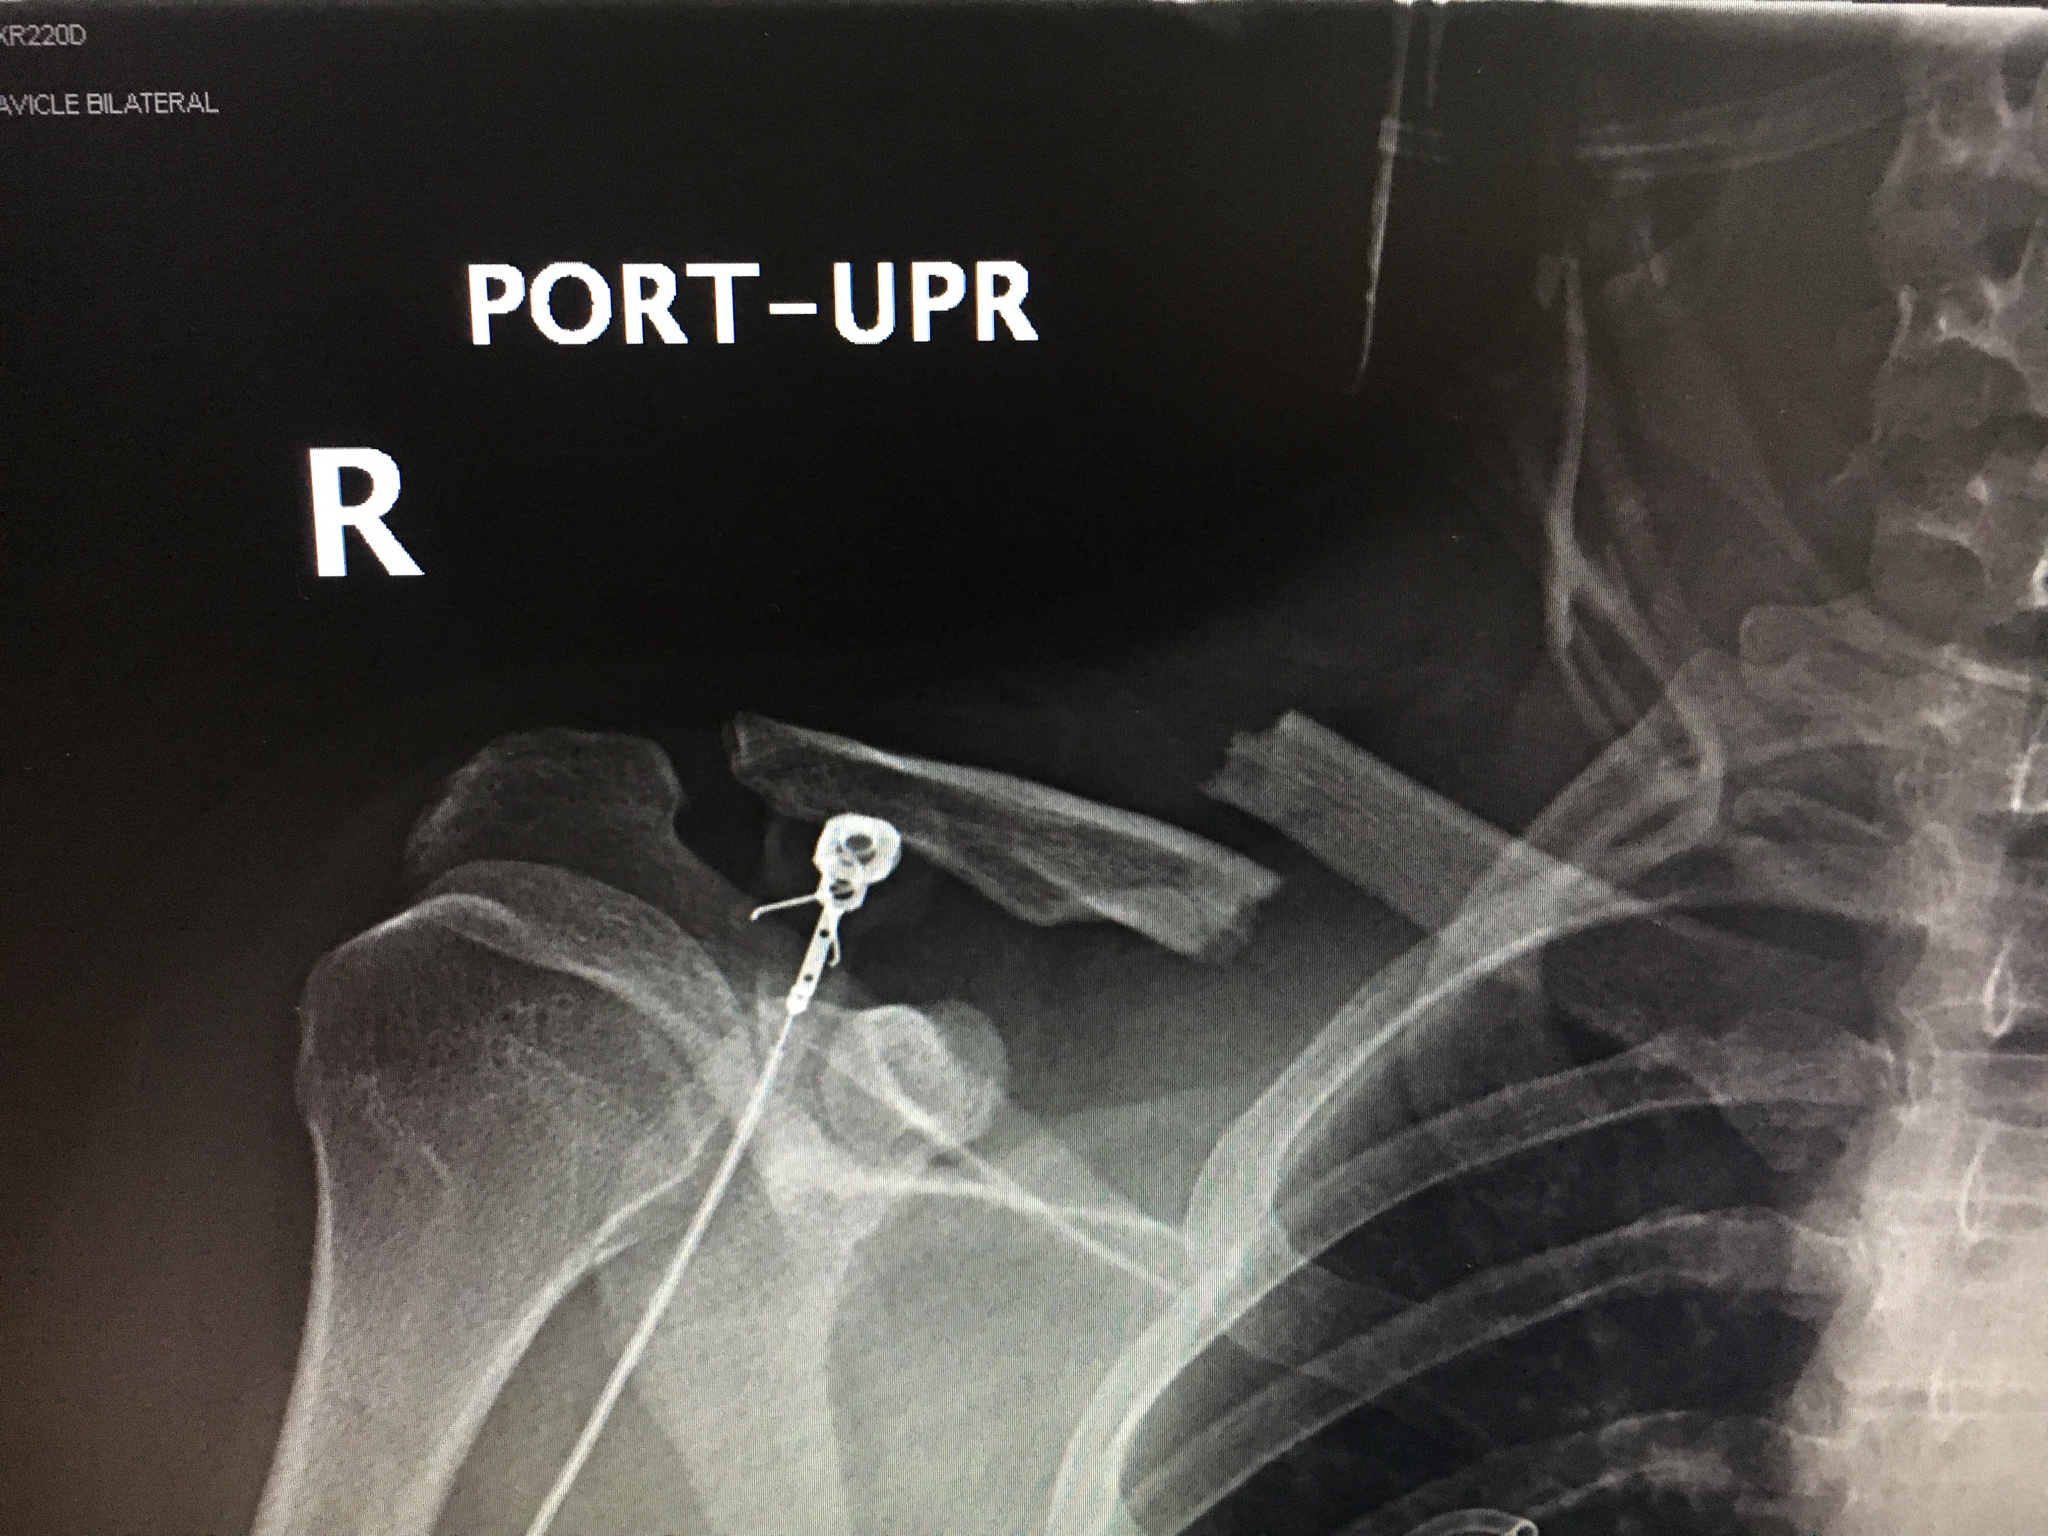

I just realized the timeline, the x ray pic was actually before the cold December pic i posted, THAT was first ride after the clavs healed lol. Hasn’t crashed hard since then and he’s 21 now so hopefully that’s the end of it ..but probably not. When moto is in your blood it’s there for good.First show him this..

and then show him this

Yeah, it’s worth it. But still not fun when you have to have your mom wiping your butt when your 19 years old. Yes, two years after the knee. It’s a rough sport.